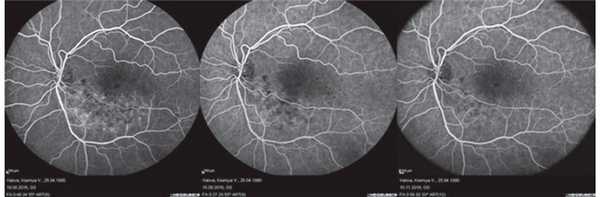

Примеры флюоресцентной ангиографии при рацемозной гемангиоме сетчатки

б) Диагностика. Наиболее информативным дополнительным методом диагностики при рацемозной гемангиоме является флюоресцентная ангиография. Во время этого исследования выявляется артериовенозное соустье, по которому быстро проходит краситель; сколько-нибудь значимое просачивание флюоресцеина отсутствует.

Клинические примеры рацемозной гемангиомы сетчатки: